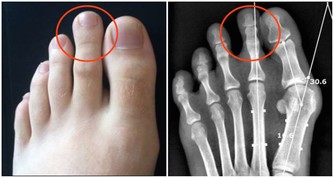

外痔:有明顯異物感

外痔發生於肛門外部,常見的主要有結締組織外痔炎性外痔,就是肉贅、皮贅或者囊腫,可能會伴隨著疼痛、瘙癢

外痔因為沒有遮掩,一般能看到或摸到,異物感非常明顯,所以往往更容易被發現。